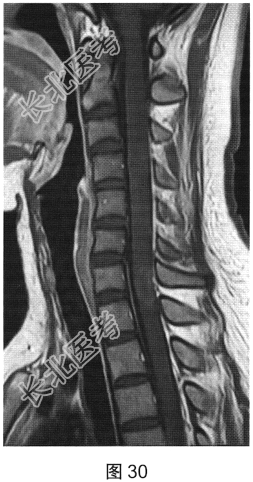

- [材料题] 患者女性,20岁,肢体无力2个月余。MRI检查结果如图27~图30所示。

- 多项选择题1.根据患者MRI平扫和增强的表现,其可能的诊断是( )

F、多发性硬化

- 多项选择题4.关于多发性硬化的诊断,叙述正确的是( )

A、“直角脱髓鞘征”是其较特征性的表现

B、脑内多发脱髓鞘病变

C、脊髓病灶多累及脊髓外周

D、病程呈复发.缓解交替

E、脊髓病灶多位于颈胸段脊髓

F、水肿及占位效应明显